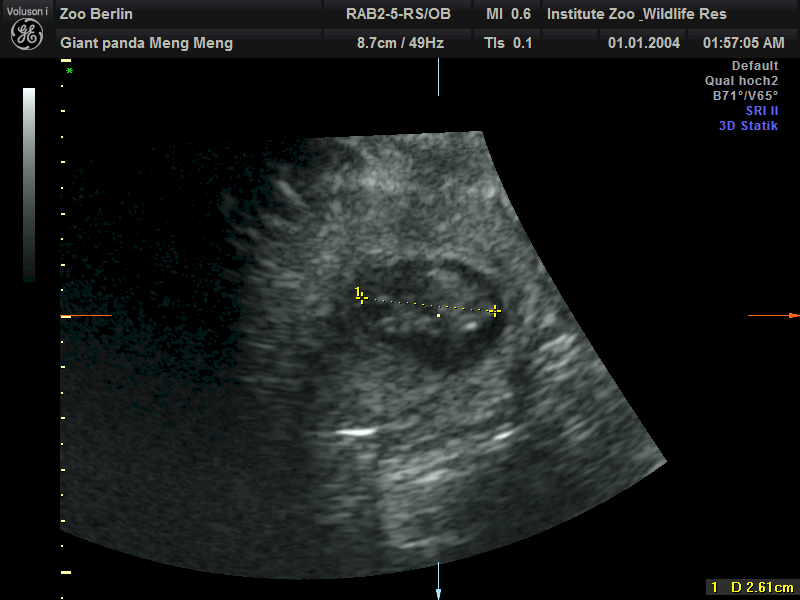

当地时间13日,德国柏林动物园在官网发布公告称,旅居柏林的中国大熊猫“梦梦”确认再次怀上双胞胎,超声检测到两个胎儿心跳。

公告表示,园区在11日的超声检测中确认了这一喜讯。目前两个大熊猫胎儿身长都约为2.5厘米。

图片来源:央视新闻客户端